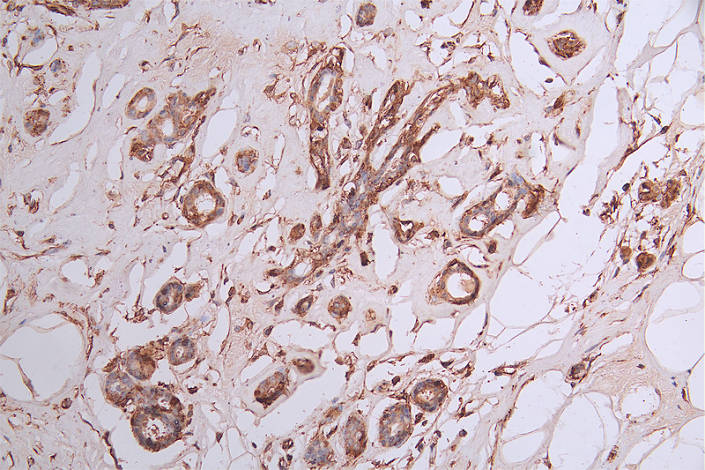

IHC image of CSB-RA029079A0HU diluted at 1:50 and staining in paraffin-embedded human breast cancer performed on a Leica BondTM system. After dewaxing and hydration, antigen retrieval was mediated by high pressure in a citrate buffer (pH 6.0). Section was blocked with 10% normal goat serum 30min at RT. Then primary antibody (1% BSA) was incubated at 4°C overnight. The primary is detected by a Goat anti-rabbit polymer IgG labeled by HRP and visualized using 0.35% DAB.